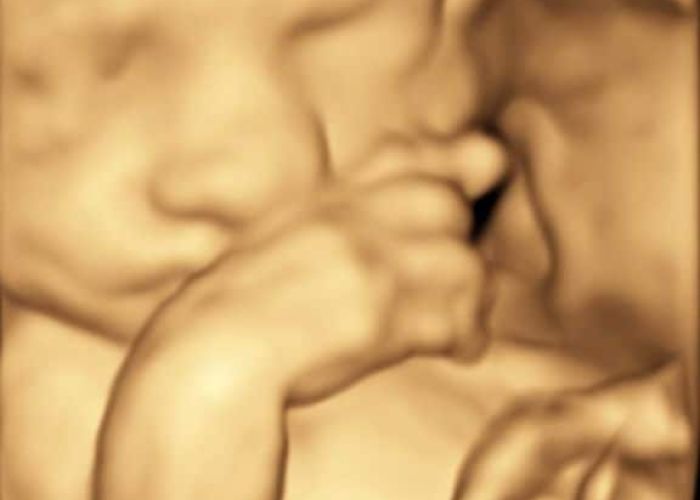

Vi tilbyder ultralydsscanninger

Ultralyd er lydbølger med så høj frekvens, at de ikke kan høres af det menneskelige øre. Man kan heller ikke mærke lydbølgerne. Lydbølgerne reflekteres af det væv de rammer og ved hjælp af avanceret udstyr dannes et billede på skærmen. Ultralydsscanning af gravide har været anvendt siden midten af 1960´erne og der er aldrig fundet tegn på skadelige virkninger – hverken hos fostret eller den gravide.

Du har mulighed for at læse meget mere om de scanninger vi tilbyder i 2D og 3D/4D scanning her på hjemmesiden. Hos Den lille jordemoder er det essentielt, at alle føler sig velkomne og trygge. Derfor er der afsat god tid til alle scanninger, således der er tid til at svare på de spørgsmål i eventuelt har om barnet eller graviditeten generelt.